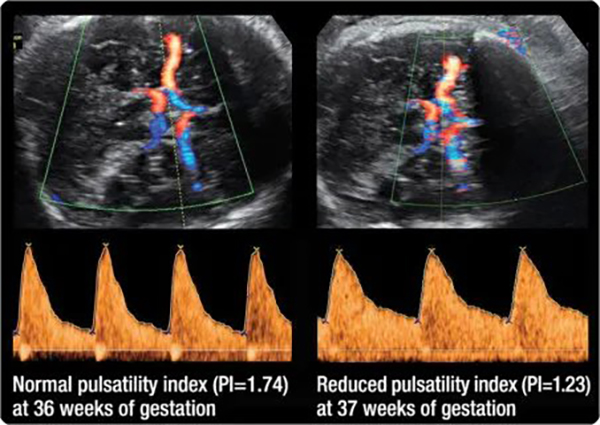

Giảm PI động mạch não giữa là hậu quả của tình trạng giãn mạch, gọi là hiệu ứng “brain-sparing”. Điều này thể hiện đáp ứng của huyết động đối với tình trạng thai thiếu oxy, thông qua đáp ứng trực tiếp của mạch máu não và ở các giường mạch máu khác diễn ra tái phân bố cung lượng tim ưu thế ở động mạch vành và tuyến thượng thận.

PI của MCA thay đổi tùy theo tuổi thai. Ở tuổi thai 28-32 tuần, phổ Doppler MCA có PSV cao và EDV thấp, PI= S-D/ mean >1,45, thai đủ tháng PI=1, thai có ý nghĩa bệnh lý khi PI< 1. Khi có hiện tượng thiếu oxy não xảy ra ở IUGR, tuần hoàn não sẽ thay đổi bằng cách giảm trở kháng để tăng dòng chảy trong thì tâm trương gọi là sự tái phân phối tuần hoàn não ( cerebral blood flow redistribution).